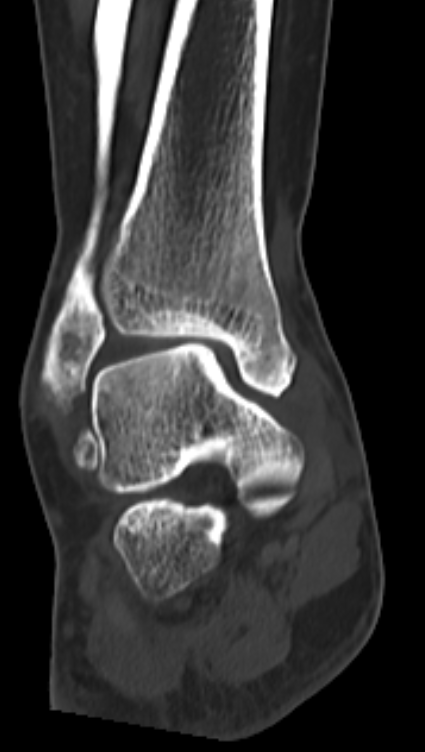

术前CT